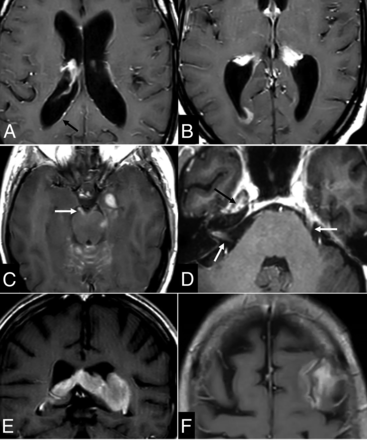

In summary, this entity should be kept in mind whenever encountering MR imaging with hemorrhage and multiple dynamic ischemic lesions on T2WI and DWI, enlarging parenchymal enhancement, and possible associated leptomeningeal or subependymal disease (Fig 5).36,37

Intravascular lymphoma (A–D). Acute patched ischemia-like lesions on DWI (A), hemorrhages (B), and an area of enhancement (C), which grows on the subsequent few days of imaging control (D). Dashed arrow in C–D indicates the growth of the same enhancing-lesion in few days. DLBCL following a lymphomatosis cerebri pattern (E–J): extensive, patched, bilateral, and diffuse FLAIR hyperintensity on the basal ganglia (E) and white matter (F), with an area of enhancement in the left cerebellum (H) and associated leptomeningeal disease (arrow in H). Intermediate CBV in DSC-PWI color maps (I) and characteristic high PSR and time-intensity curve morphology (J). Tumoral pattern on 1H-MR spectroscopy at long TE with a high Cho-to-NAA ratio (H) and absent mIns at the short TE (not shown), helpful in the differential diagnosis with nontumoral entities and gliomatosis cerebri, respectively.

On conventional imaging, they appear as extra-axial lesions with a wide dural base, soft attachment angles, and a possible CSF cleft between the lesion and brain parenchyma. In addition, edema or brain tissue infiltration can occur. They usually appear homogeneous, NCCT hyperattenuated, T2WI hypointense, and with restricted diffusion; however, these features overlap with those of the most frequent extra-axial tumor in adults, meningioma (Fig 6).39,40

Dural lymphomas. MALT dural lymphoma (A–D) with extra-axial lesion features such as a CSF cleft (A) and a wide-implantation dural base with soft marginal angles (C), as well as T2-hypointensity (A) and diffusion restriction (B). Almost normal calvarial bone; only subtle sclerosis seen (D), despite the great soft-tissue component on both sides of the diploe (A–C). Similar imaging features with minimal bone destruction and a subtle permeative pattern (F) in comparison with the prominent soft-tissue component (E) in another diffuse large B-cell dural lymphoma (E and F).

A clue for the presurgical suspicion of this tumor is provided by a characteristic pattern of bone infiltration or transdiploic extension. Characteristically, lymphoma presents as an extensive soft-tissue mass without bone destruction (normal bone to subtle permeative patterns) (Fig 6). This pattern is explained by the extension of tumor cells through Haversian canals. It differs from what is seen in meningiomas with hyperostosis or in plasmacytoma or metastasis with aggressive lytic destruction.39